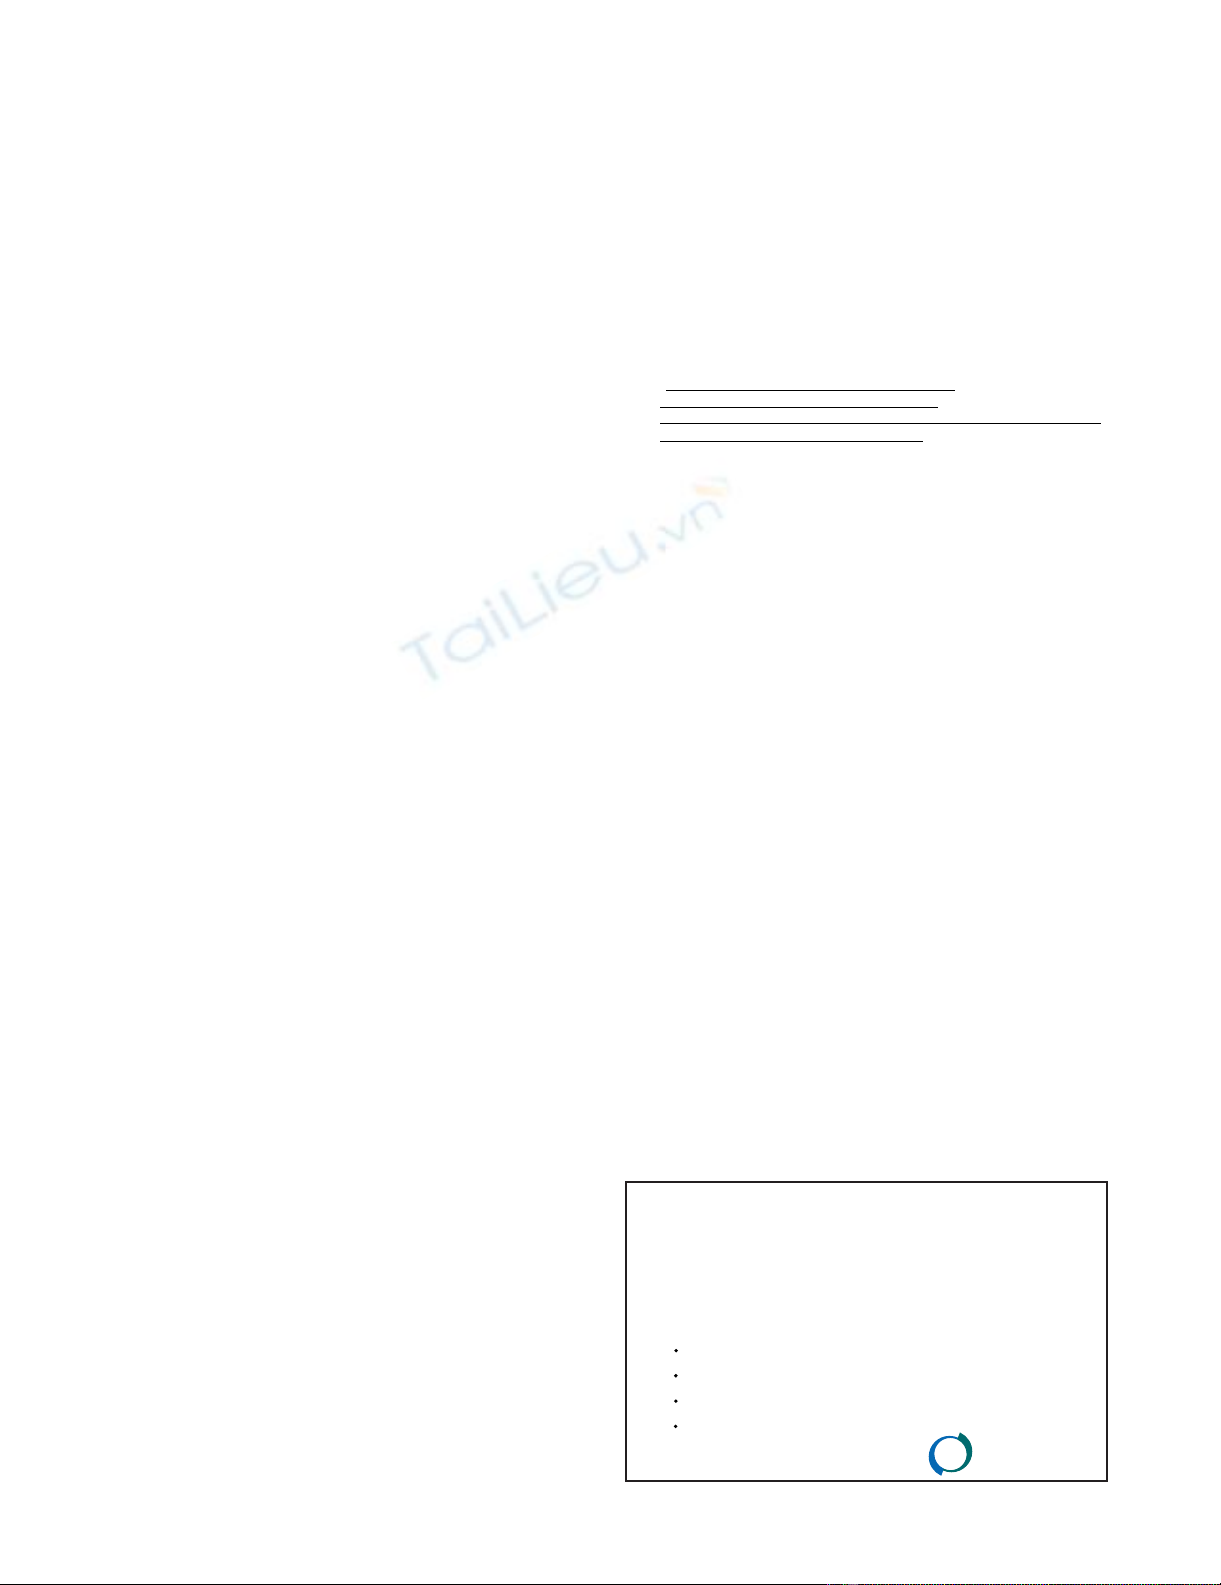

The patient tolerated the procedure well and was sent

home after a 14-day hospitalization. The postoperative

course was complicated by the formation of a subhepatic

abscess that was successfully treated with drainage cathe-

ters and systemic antibiotics. Imatinib was discontinued

approximately one month after surgery for a total of one

year of therapy. Follow-up CT 6 months after surgery

demonstrated no residual neoplastic disease (Figure 4a,

4b). At fourteen-months follow up, the patient was found

to be doing very well with no evidence of recurrent dis-

ease.

Computerized tomography A) and B); no evidence of meta-static diseaseFigure 4

Computerized tomography A) and B); no evidence of meta-

static disease.